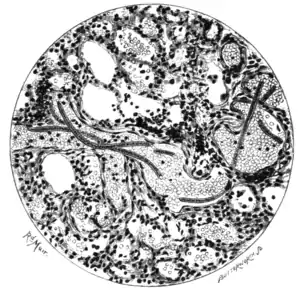

Fig. 100.—Section of lung showing microfilariæ in the blood-vessels.

(From a microphotograph by Mr. Spitta.)

Since this was written they have been found in the spleen tissue by other observers. The capillaries of the lung appear to be the favourite habitat of microfilariæ. Microfilaria immitis, mf. perstans, and the non-periodic Fijian microfilariæ have been found in greatest abundance in this situation.